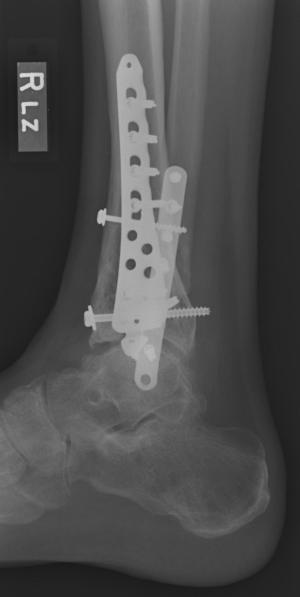

Post-infection X-Rays of the damaged right & left legs / ankles

After the last surgery Liam developed Staphylococcal (staph) infection as well as Osteomyelitis on the bone. Liam went to the ER of

Tempe St. Luke with a temperature of over 104 degrees and severe pain of the left leg. Liam was released from the ER with a diagnosis of

Gastroenteritis and instructions to follow up with a visit to Dr. Armendariz. Four days later and with a continued very high temp, Liam was

seen by Dr. Armendariz. Dr. Armendariz immediately performed 3 surgeries to clean out the infected areas of both the left and right leg and

to place wound vacs on the damaged areas of the legs.

An interesting point to note, as it applies to the second and third x-rays (from the left), is the placement of the last screw at the bottom

of the right legs fibula plate. Notice how Dr. Keller completely missed the plate. Not only is the screw useless, but it has started protruding

in such a way as to cause severe pain and require padding to keep from bursting through the skin. A later surgery is planed for the screws

removal.